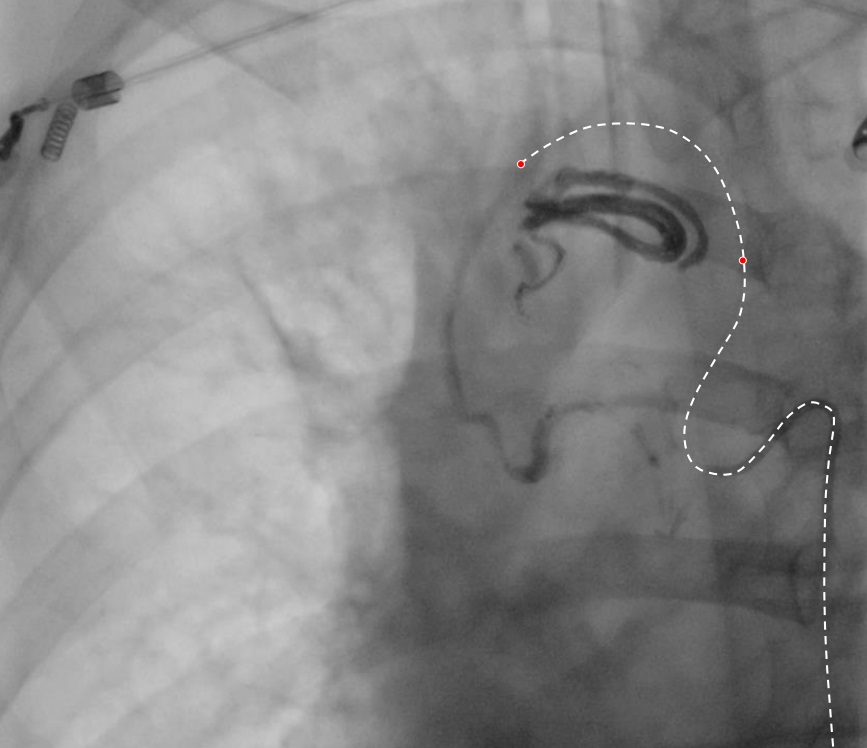

反流期

EVOH: 不一样的特性 Unique properties• 甚至可能逆血流主动分布 Active distribution even against blood stream possible

一 和NBCA,酒精血流相关被动分布相反,Onyx 逆血流主动分布 As opposed to passive, flow-related distribution (NBCA, alcohol)

– 主动血流分布,甚至逆血流分布(血管塞和推进技术)Active distribution, even against the flow (plug & push technique)